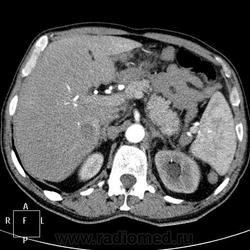

Пациент 71 года, поступил с подозрением на тромбофлебит правой нижней конечности. После УЗИ ОБП (не могу предоставить иллюстрации), переведен в онкологическое отделение с диагнозом мтс печени и забрюшинных лимфоузлов. Рентгенография ОГК, ФЭГДС - без особенностей. Колоноскопия - сигма непроходима аппаратом из-за сдавления извне.

артериальная фаза:

Источник мтс-опухоль левой стенки мочевого пузыря?

Однозначно мета в печени, забрюшинные узловые образования, подобные образования в правой подвздошной области, пораженная стенка мчевого пузыря (инфильтративный рост). Левый мочеточник видится тоже измененным(?), гидронефроз слева. Полистать бы сериию, а так складывается впечатление о раке мочевого с mts в регионарные и забрюшинные лимфоузлы, печень...

С уважением, С.Н. Нагорный

Я тоже поставила первичным рак мочевого пузыря. Пациент уехал в областной онкодиспансер.